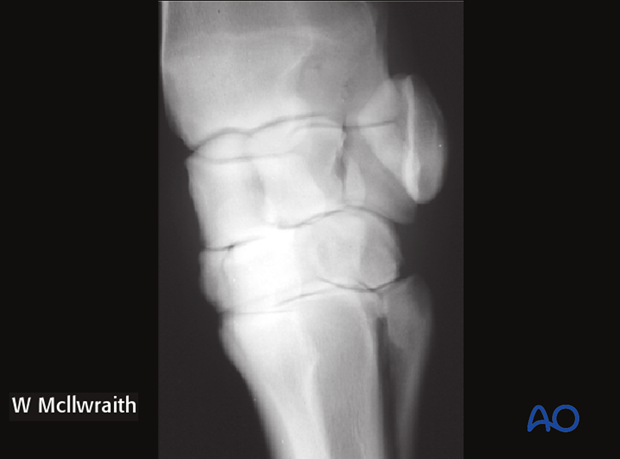

Frontal fractures of the radial facet of the third carpal bone can be non-displaced or displaced. Both instances present with lameness and joint effusion. The nature of the fracture is confirmed with radiographs.

These fractures are demonstrated with:

This x-ray shows a complete non-displaced fracture in the skyline view.